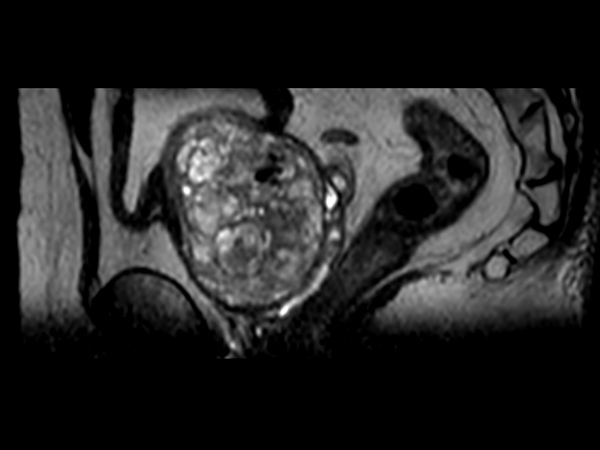

Multi-phase, contrast-enhanced prostate imaging

Patient with a prostate lesion. The ExamCard includes techniques for 3D imaging (PelvisVIEW, eTHRIVE) allowing for multiple image directions in one single scan, efficient fat-free imaging over large field-of-views (mDIXON XD), a multi-phase contrast-enhanced sequence (4D FreeBreathing) to improve imaging confidence and Compressed SENSE to accelerate the entire exam.